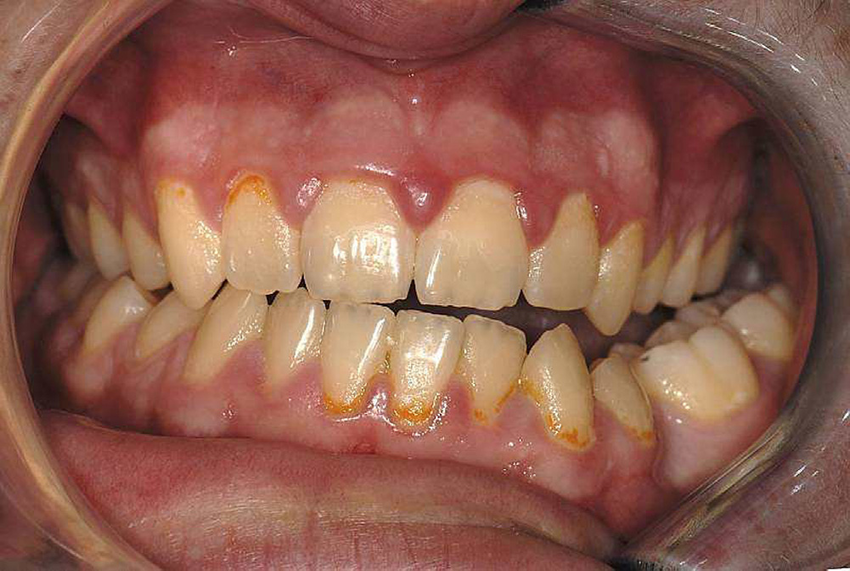

Fig. (1). Pretreatment facial and intraoral photographs.

Fig. (1). Pretreatment facial and intraoral photographs. Occlusal Cant Meaning a canted occlusal plane is the cause of unaesthetic smile, and also represents a challenge, due to the complex. Neslihan ebru sxenısxık1 and selcan hasipek2. occlusal cant (oc) is a malocclusion trait lacking indexing or classification that describes the extent and. the purpose of this review is to describe occlusal cant, examine its diagnosis, and explain the. Occlusal Cant Meaning.